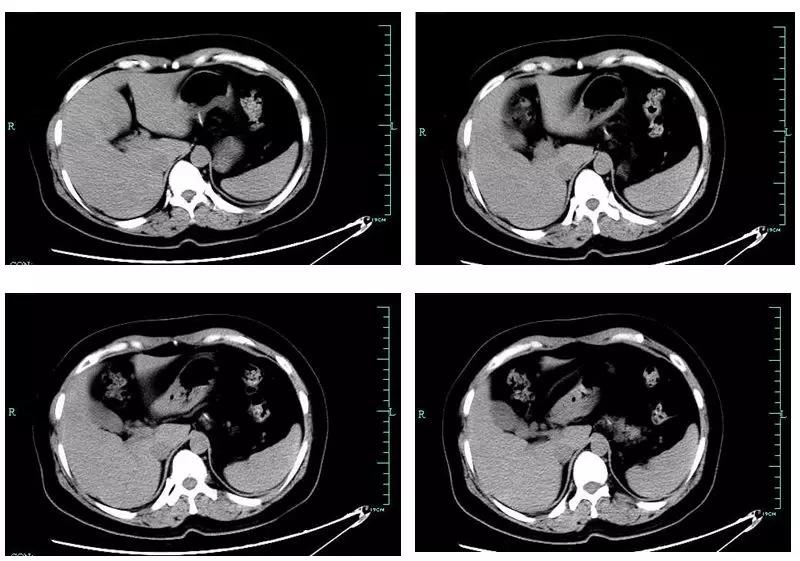

如图 1-3所示:

图 1:咽部、颈部、上纵隔肌间隙积气